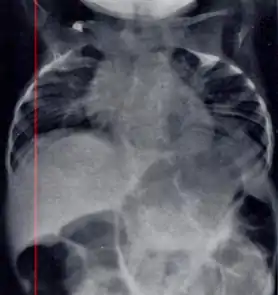

| Radiograph depicting typical skeletal features of Jarcho-Levin syndrome, subtype spondylothoracic dysplasia. Note fanlike configuration of the ribs, with extensive posterior fusion, along with multiple vertebral segmentation defects. | |

Spondylothoracic dysplasia

Spondylothoracic dysplasia, or STD, has been repeatedly described as an autosomal recessively inherited condition that results in a characteristic fan-like configuration of the ribs with minimal intrinsic rib anomalies. Infants born with this condition typically died early in life due to recurrent respiratory infections and pneumonia due to their restricted thorax.[3][4][5] Recently, a report[6] has documented that actual mortality associated with STD is only about 50%, with many survivors leading healthy, independent lives.

In contrast to STD, the subtype spondylocostal dysostosis, or SCD features intrinsic rib anomalies, in addition to vertebral anomalies. Intrinsic rib anomalies include defects such as bifurcation, broadening and fusion that are not directly related to the vertebral anomalies (such as in STD, where extensive posterior rib fusion occurs due to segmentation defects and extreme shortening of the thoracic vertebral column).[6] In both subtypes, the pulmonary restriction may result in pulmonary hypertension, and have other potential cardiac implications.[7]